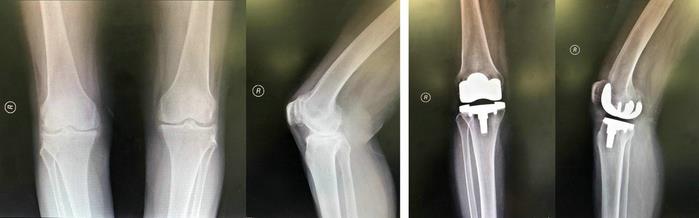

第四阶梯适用于关节磨损严重、上述治疗手段均无效的患者。在全身情况能耐受手术的条件下,可行人工关节置换术,这是目前公认的消除疼痛、矫正畸形、改善功能的有效方法。通过将人体老化磨损的关节面替换成光滑的人工关节面,达到使关节“焕新”的目的,从而彻底解除疼痛症状,恢复膝关节功能,彻底治疗骨性关节炎,大大提高患者的生活质量。

膝人工关节置换术前术后X线片